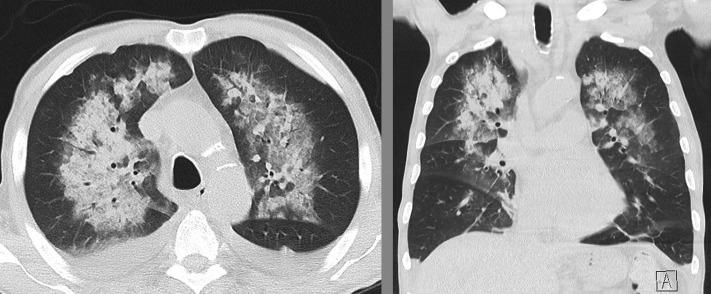

两例免疫功能低下患者并发弥漫性肺泡出血,为严重新型冠状病毒病 2019 的并发症。

Two Immunocompromised Patients With Diffuse Alveolar Hemorrhage as a Complication of Severe Coronavirus Disease 2019.

Diffuse alveolar hemorrhage (DAH) is a severe and potentially life-threatening disease manifestation. In addition to autoimmune diseases such as antineutrophil cytoplasmic antibody-associated vasculitis and anti-glomerular basement membrane syndrome, pulmonary viral infections are known to be culprits of DAH. Health-care providers worldwide in the coronavirus disease 2019 pandemic have been confronted with an unprecedented number of viral lung infections, with great variance in symptoms and severity. Hemoptysis, the key symptom of DAH, is a rare complication. We present two cases of immunocompromised patients with rapidly developing hypoxemic respiratory failure and evidence of DAH in the context of severe acute respiratory syndrome coronavirus 2 infection.

摘要

弥漫性肺泡出血 (DAH) 是一种严重且可能危及生命的疾病表现。除了抗中性粒细胞胞质抗体相关性血管炎和抗肾小球基底膜综合征等自身免疫性疾病外,肺病毒感染也已知是 DAH 的罪魁祸首。在 2019 年冠状病毒病大流行期间,全球的医疗保健提供者面临着数量空前的病毒性肺部感染,症状和严重程度差异很大。咯血是 DAH 的关键症状,但较为罕见。我们报告了两例免疫功能低下患者的病例,他们在严重急性呼吸综合征冠状病毒 2 感染的背景下迅速出现低氧血症性呼吸衰竭和 DAH 的证据。